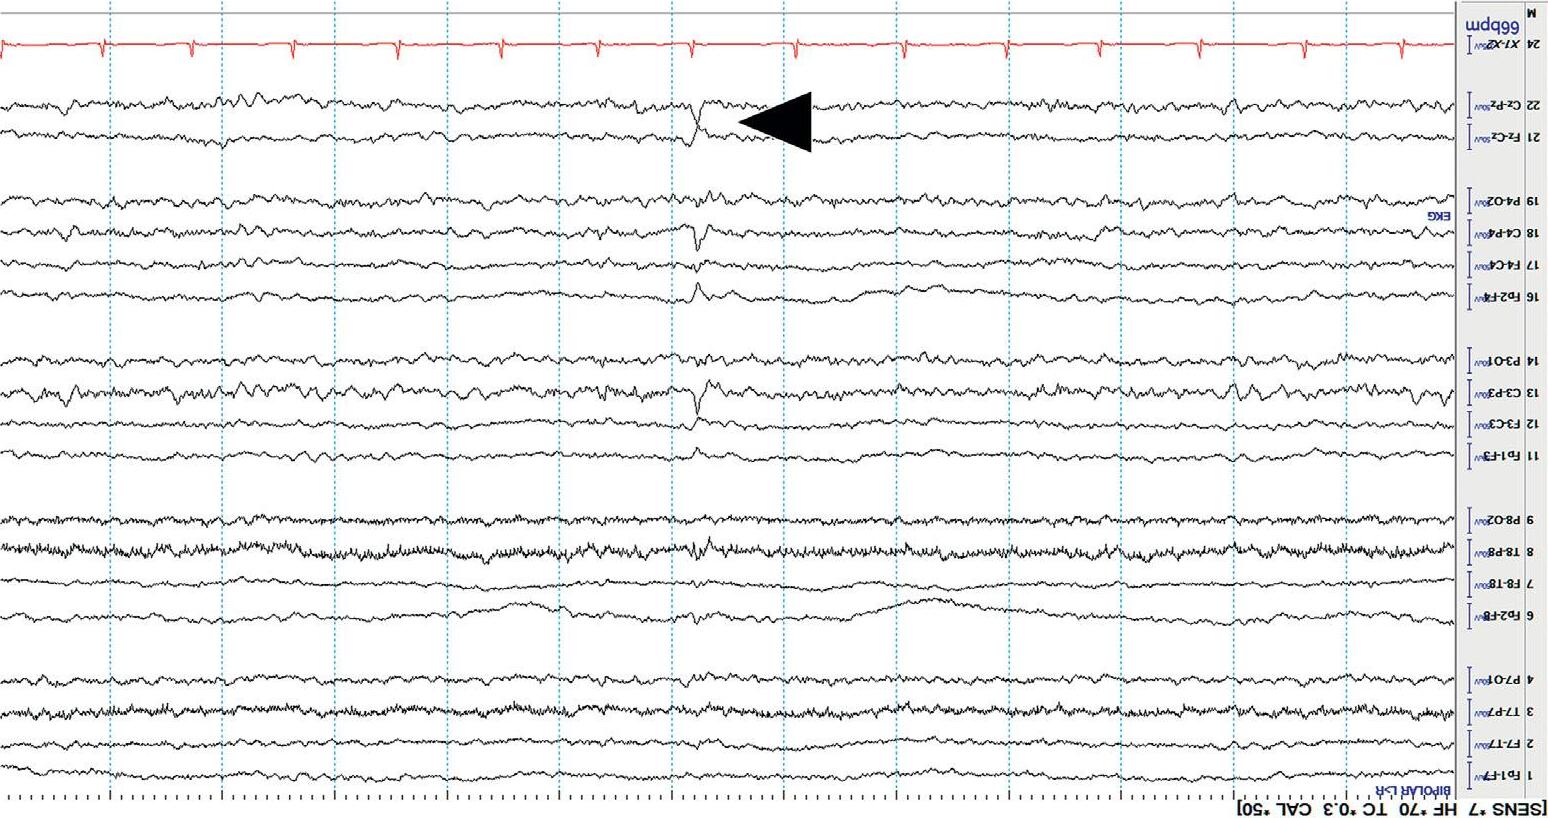

Thekeytolocalizationisanelectrographicprinciplecalleda phasereversal. ThisisasimultaneousbutoppositedeflectionintwoadjacentEEGchannels containingacommonelectrode.Aphasereversalimpliesthatthecortical potentialismaximalatthelocationofthecommonelectrode.

Mostphasereversalsarenegative(><),thoughrarelypositivephase reversals(<>)mayoccur. Figure1.4 showsanexampleoflocalizingafocal sharpwave.

Figure1.4 Localizingasharpwave(blackarrow)throughphasereversaltoelectrodeP8(blackcircle).